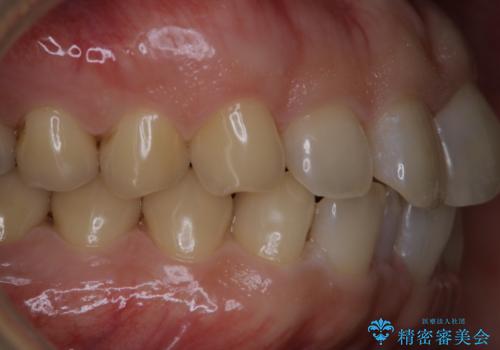

細かいステインをPMTCでOFF

- 歯ブラシをしてもとれないステインが気になるとのことで来院されました。PMTC60分コースを行いました。

PMTCは、歯に付着した汚れを除去していくため、着色が気になる場合にも行うことができます。ご自身でのセルフケアだけで着色を落とそうとすると、逆に歯を傷つけてしまったり、精密に汚れを除去できないこともあります。また、日常生活で着色しやすい飲食物を避けたりすることはストレスに感じてしまったり、あまり現実的ではありません。

毎日丁寧に歯磨きをしていても、日常生活での飲食物などにより着色してしまうことはあります。PMTCでは、歯の表面の凸凹にミネラルを補給して、ツルツルの表面に仕上げます